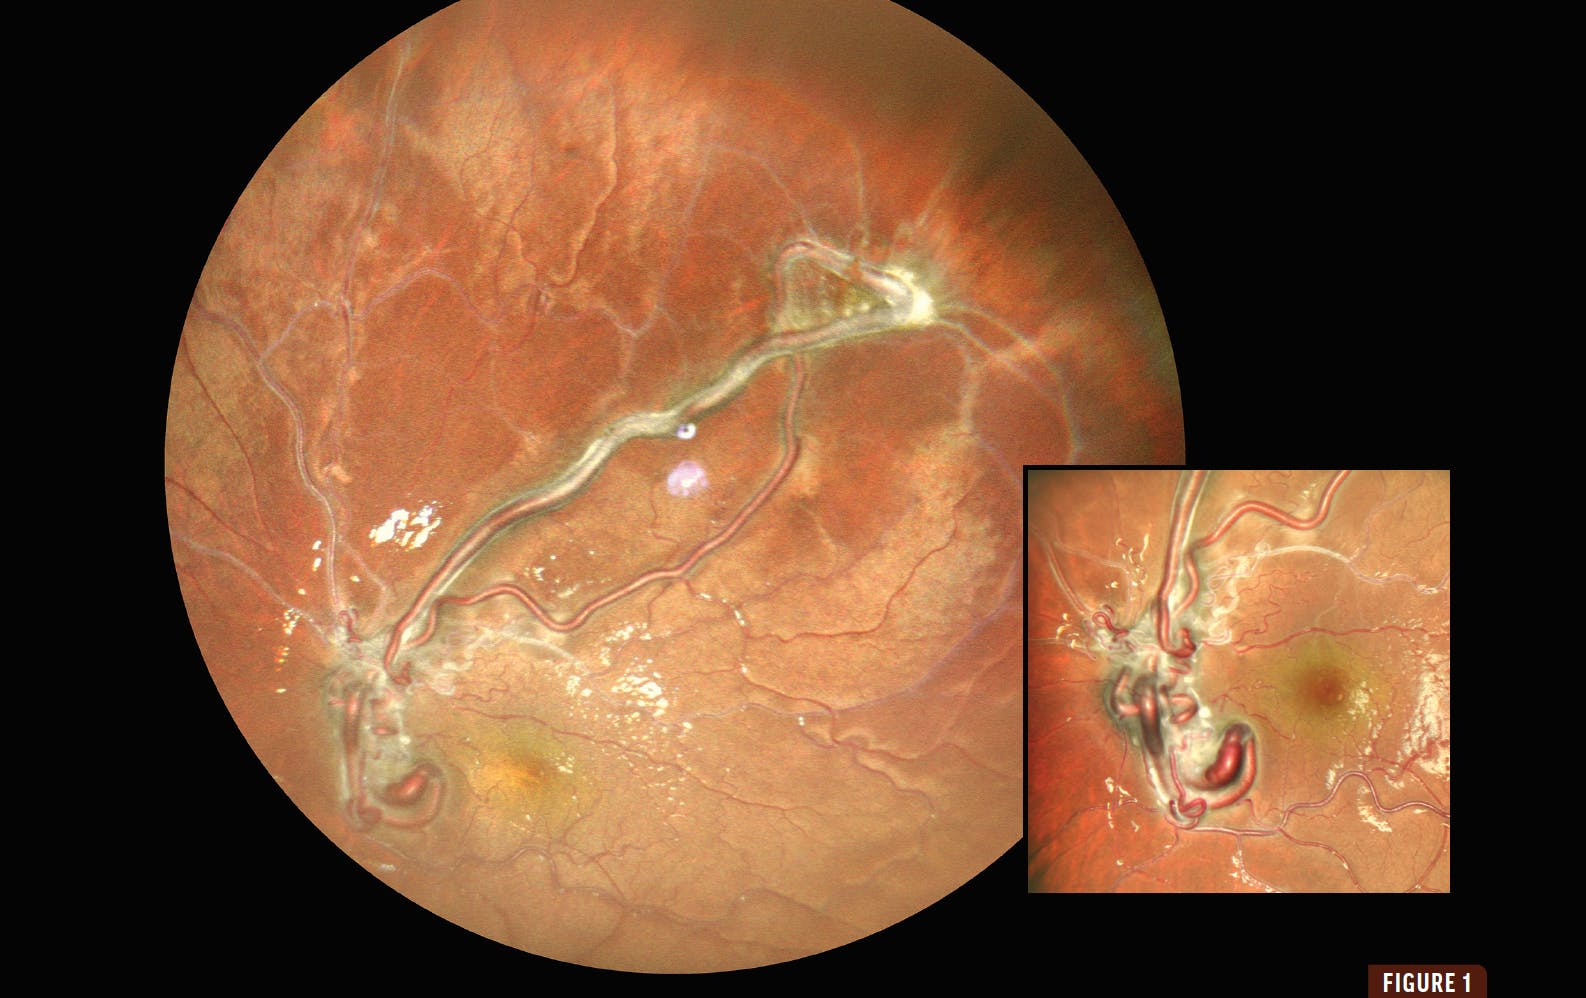

A 10-year-old girl presented with a 3-month history of reduced vision in her left eye. Her VA was 20/20 OD and 20/200 OS. Fundus examination of her left eye revealed markedly dilated, corkscrew-like arteriovenous channels with perivascular sheathing that extended from the optic disc into the superotemporal retina (Figure 1). OCT revealed large hyperreflective intraretinal vessels with posterior shadowing and a normal foveal contour (Figure 2). Fluorescein angiography revealed rapid filling of the arterial and venous components with minimal transit time with no associated leakage (Figure 3).

Based on these findings, the patient was diagnosed with racemose hemangioma in her left eye. Neuroimaging to rule out Wyburn Mason syndrome was negative.